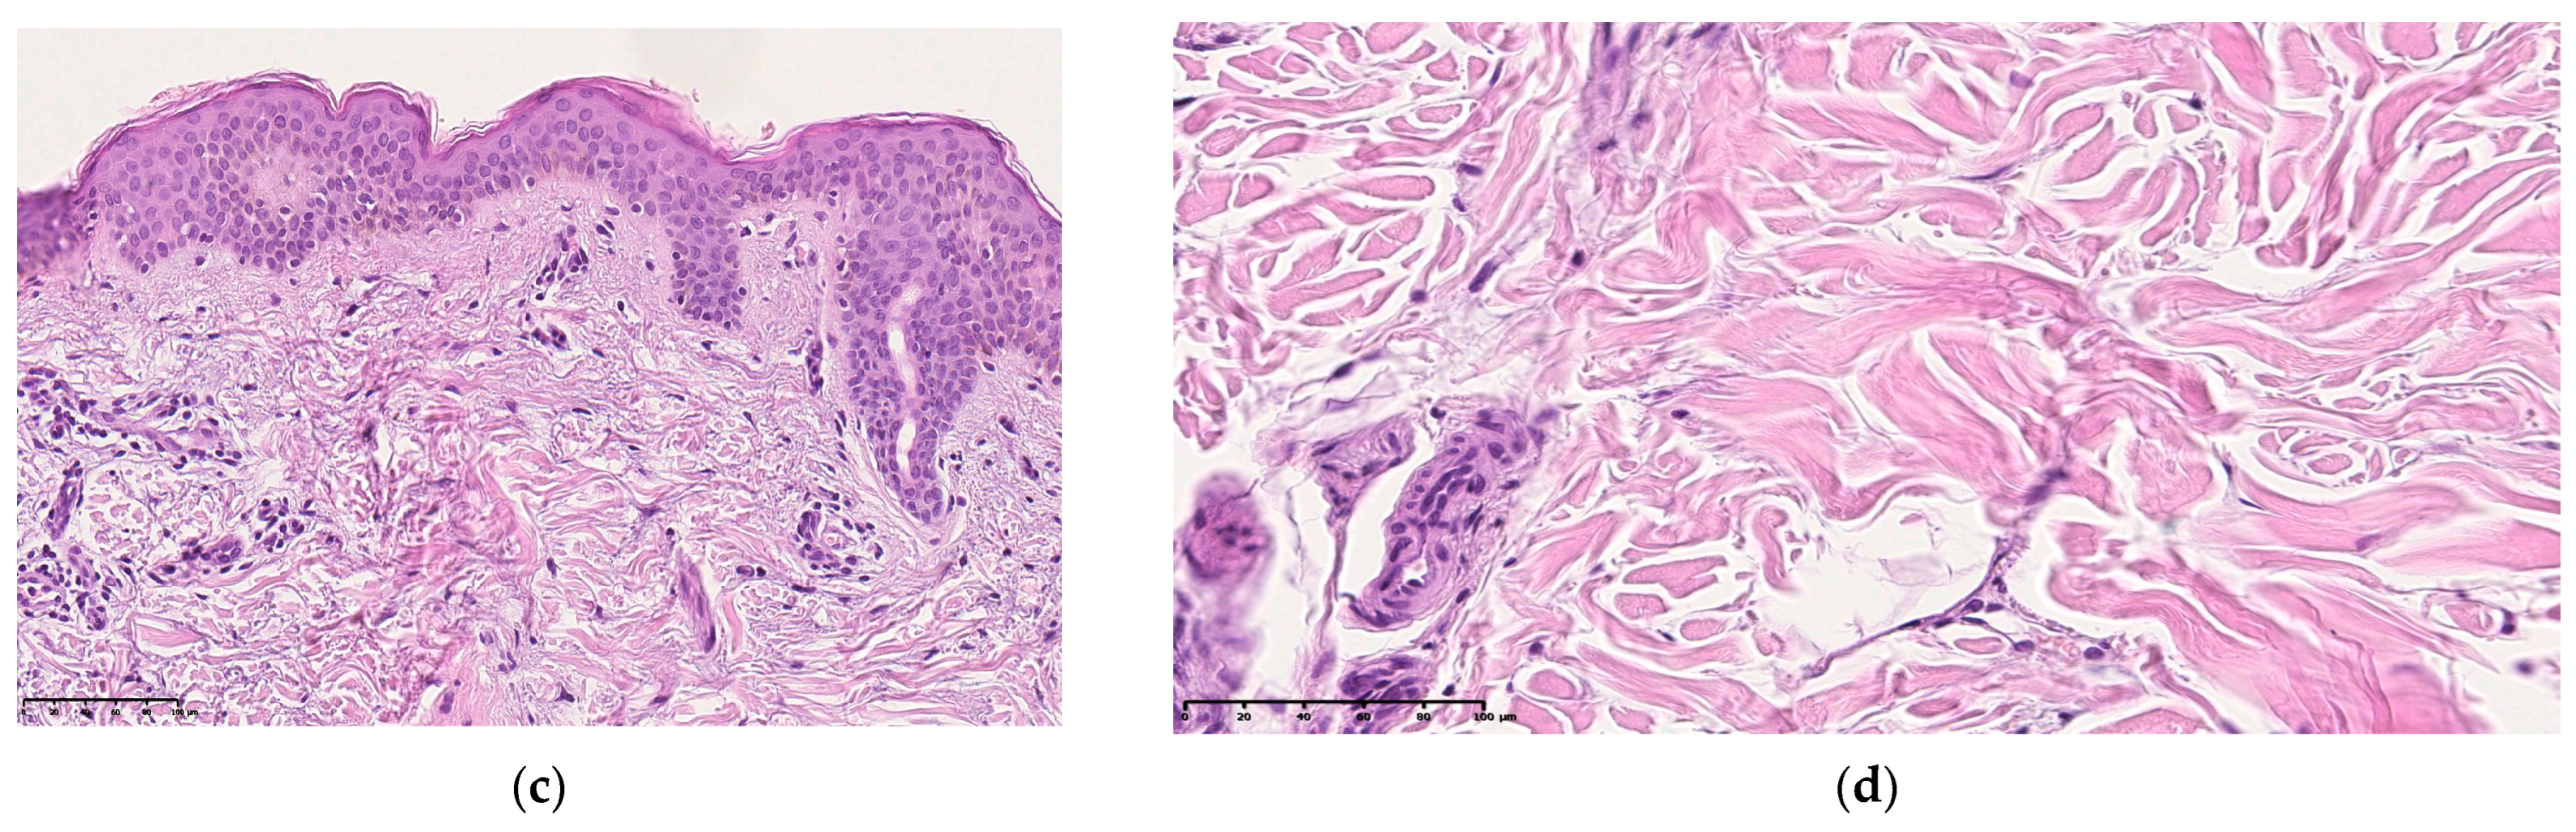

Histological examination of skin sections of patients with premature aging revealed a decrease in the thickness of the epidermis, mainly due to a decrease in the number of rows of cells of the spinous layer. The rate of keratinization of the epidermis is increased, the morphological manifestation is an increase in the thickness of the stratum corneum and its detachment from the underlying layers of the epidermis. The granular layer is weakly expressed. The undulation of the border between the papillary dermis and the epidermis is enhanced. The folding of the skin is more pronounced, the morphological manifestation of which is an increase in the height of the epidermal papillae, which look narrow and long on slices. In the papillary layer of the dermis, the fibers are thinner, the degree of their heterogeneity is pronounced, there is a decrease in the inter-fiber gaps, leading to a decrease in the thickness or its area of the papillary layer. The cell density is slightly higher than in the group of patients with normal skin aging. The border between the papillary and reticular layers of the dermis of the skin is more contrastingly pronounced (Figure 5).

Figure 5.

Micrography of the skin section in the main group is an intact skin area of patients with premature skin aging: (a–c) stained with hematoxylin and eosin, (d,e) stained according to the Van Gieson method. ×100 (a,b,d), ×200 (c,e).

In the reticular layer, the bundles of collagen fibers are coarse and deformed, and their heterogeneity is pronounced. The area of inter-fiber gaps has been reduced.